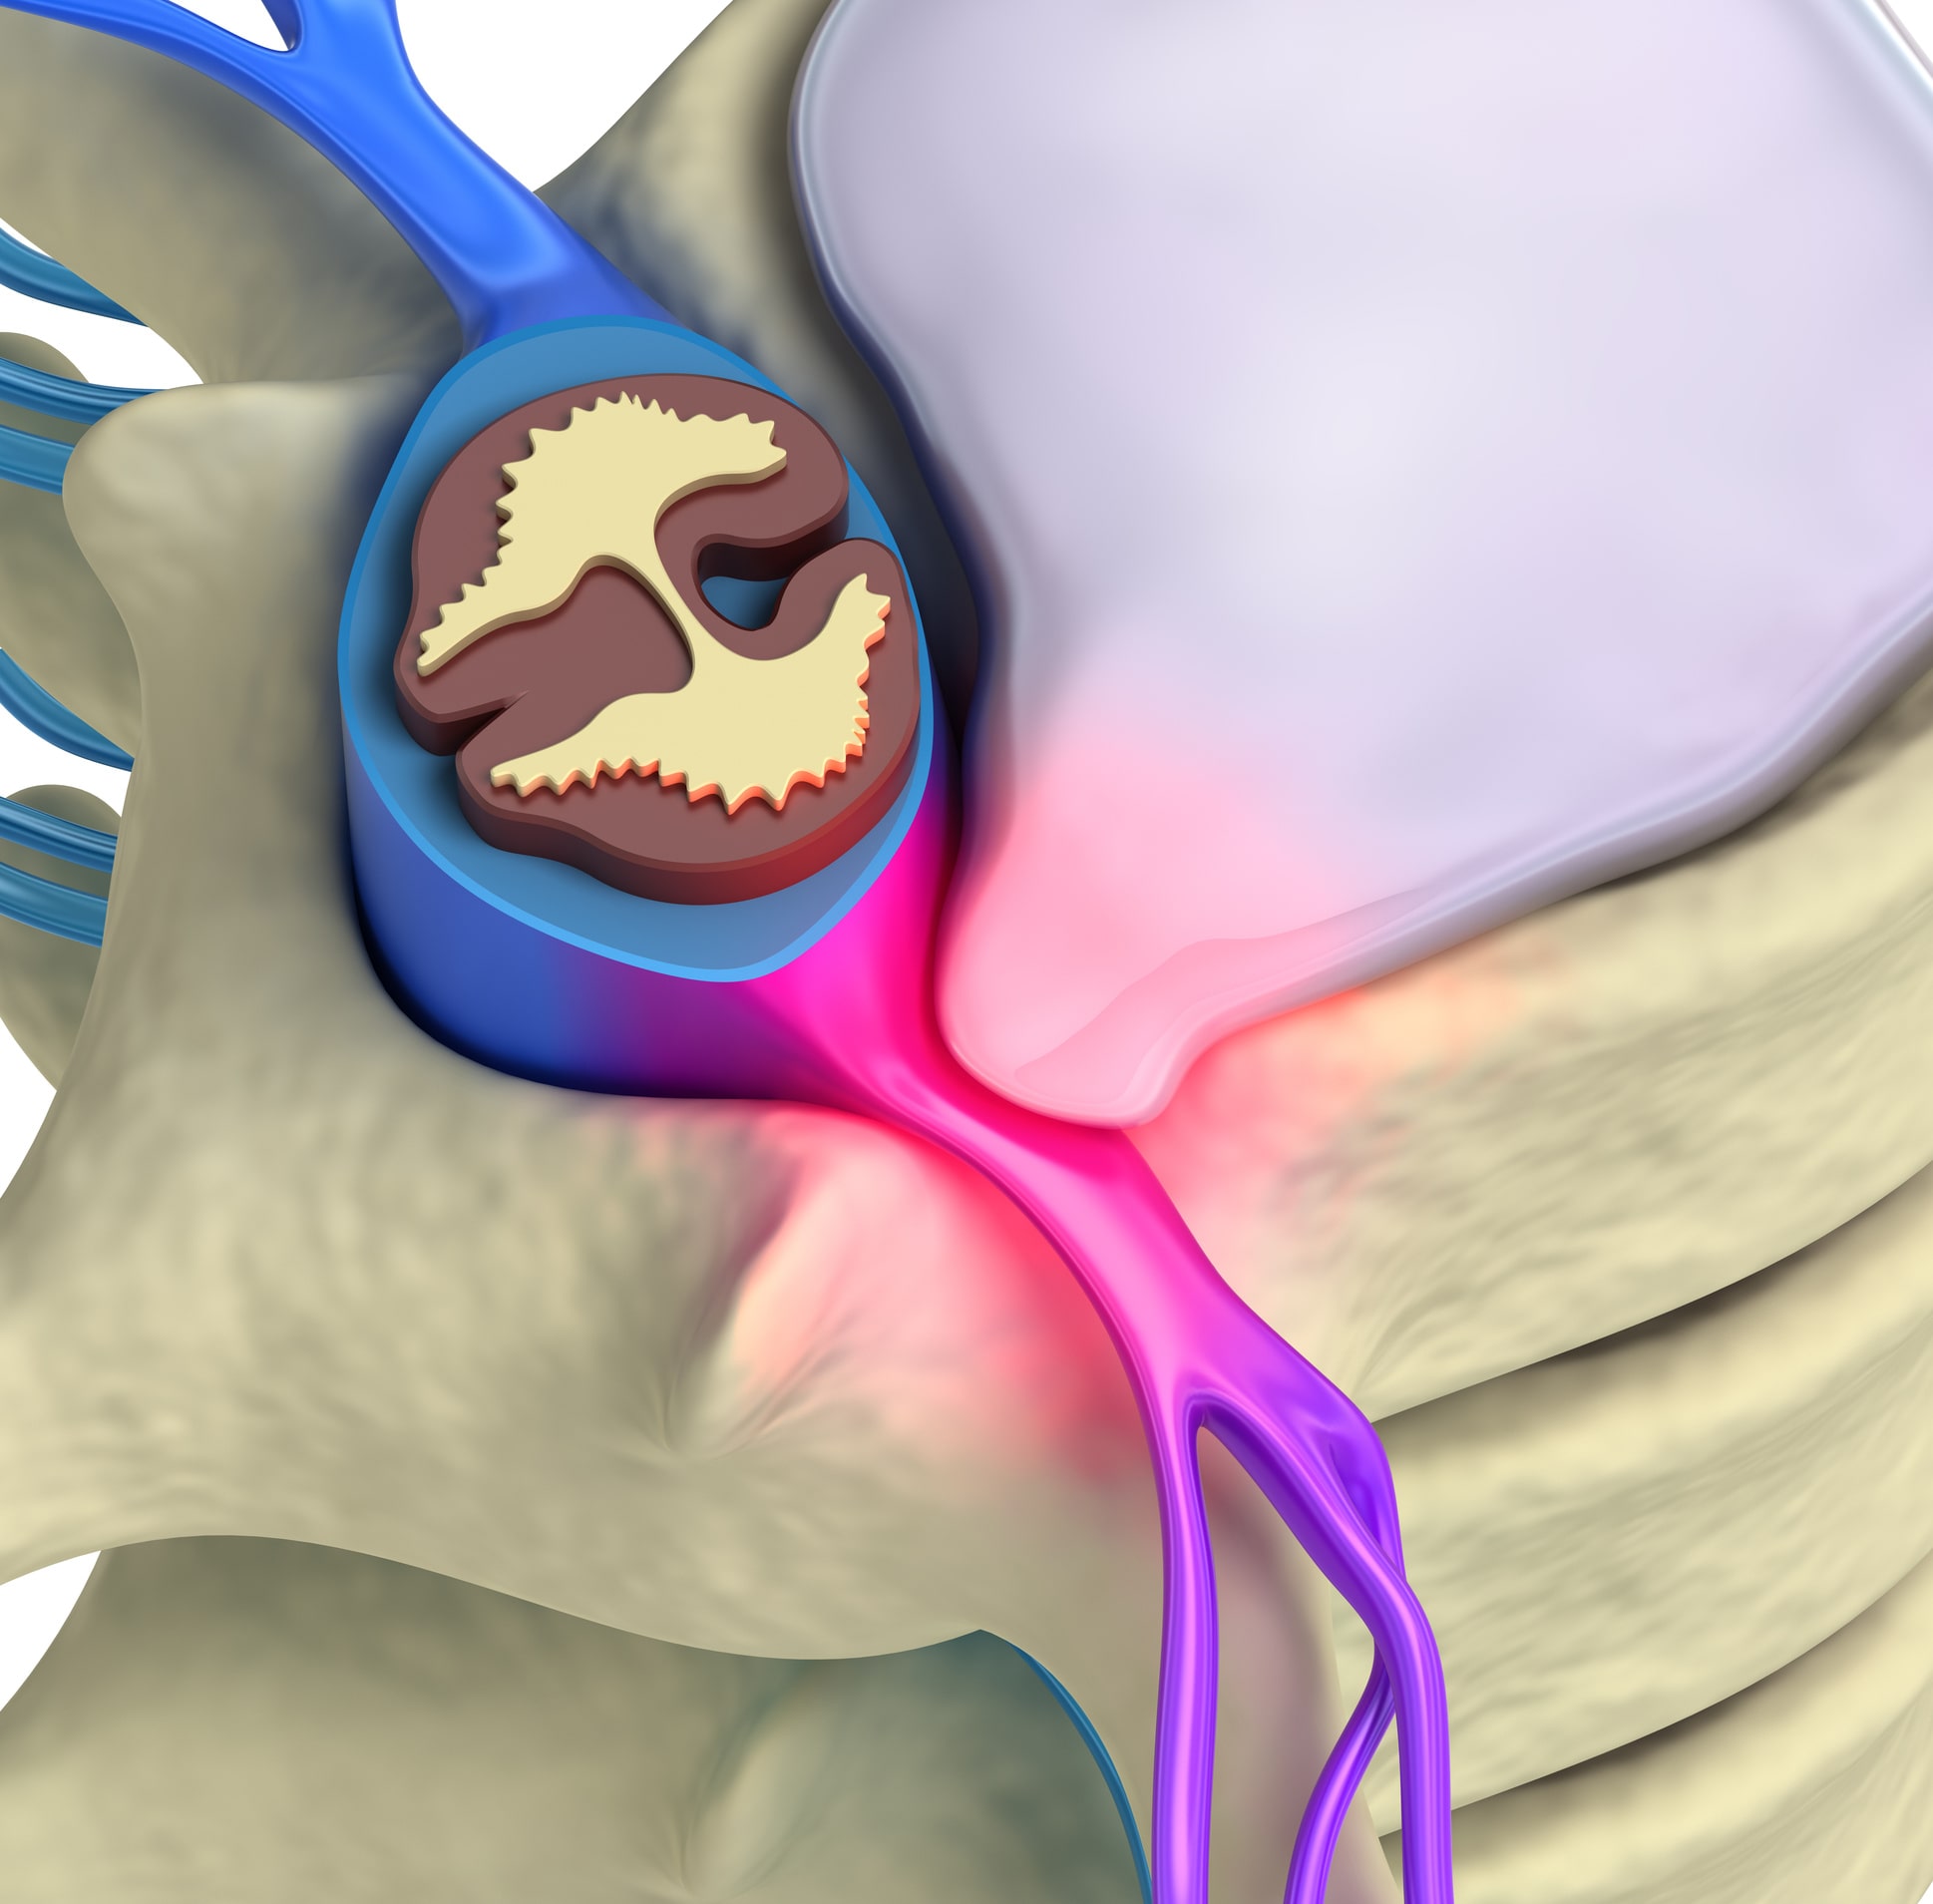

HERNIA DISCAL.

Una hernia discal se produce cuando material del disco intervertebral se sale de su sitio. El disco intervertebral está compuesto por un anillo de fibras de colágeno que contiene en su intención un material gelatinoso denominado núcleo pulposo. Se produce una hernia cuando las fibras del anillo se degeneran, se vuelven más laxas y se abomban y el núcleo pulposo ocupa este abombamiento. En ocasiones el anillo fibroso se rompe y el núcleo pulposo sale al espacio epidural, es lo que se denomina hernia discal estrusa. Una hernia discal da como síntoma principal una ciática.

La ciática se caracteriza por ser un dolor que baja por toda la pierna y que se asocia a calambres, hormigueos y dolor de espalda.

Cuando tenemos una ciática hay movimientos concretos en los que aumentan el dolor, por eso intentamos mantener la postura que no nos produce dolor y se producen lo que se denominan contracturas musculares anti-álgicas.